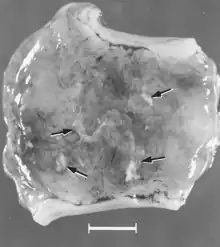

There are numerous macroscopic changes in fetuses infected before they become immunocompetent (Fig. 6). These include a variable degree of stunting and sometimes an obvious loss of condition before other external changes are apparent; occasionally, an increased prominence of blood vessels over the surface of the fetus due to congestion and leakage of blood into contiguous tissues; congestion, edema, and hemorrhage with accumulation of serosanguineous fluids in body cavities; hemorrhagic discoloration becoming progressively darker after death; and dehydration (mummification). Many of these changes also apply to the placenta. Microscopic lesions consist primarily of extensive cellular necrosis in a wide variety of tissues and organs[95][98] (Fig. 7A). Inflammation[98] and intranuclear inclusions[95] also have been described.